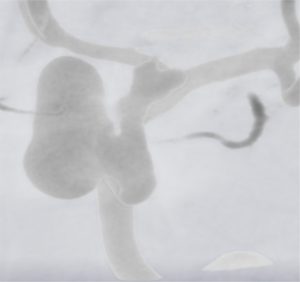

Typical raw data from an angiogram taken of a patient with a unilateral aneurysm. The blood vessels and aneurysm are more highly resolved than the surrounding tissue and bone in this type of imaging.